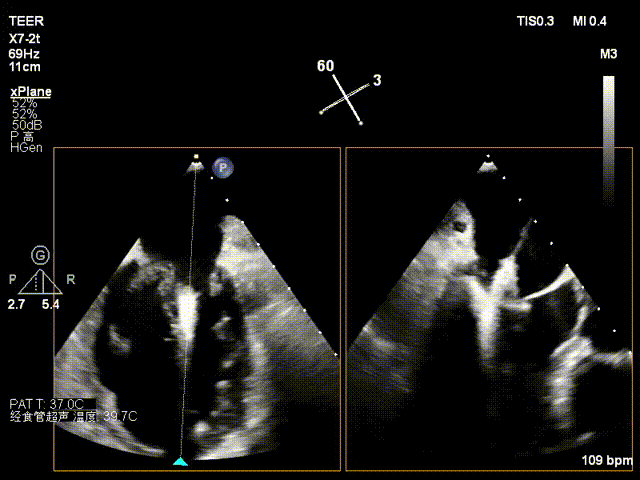

患者为73岁老年男性,经食道超声检查提示:急性二尖瓣腱索断裂合并反流,前叶长度:2.8cm,后叶长度:1.7cm,脱垂宽度:18mm,脱垂高度:8mm,瓣口面积:6.5cm²。

术前影像

左房极小

房间隔增厚

X-plane2区